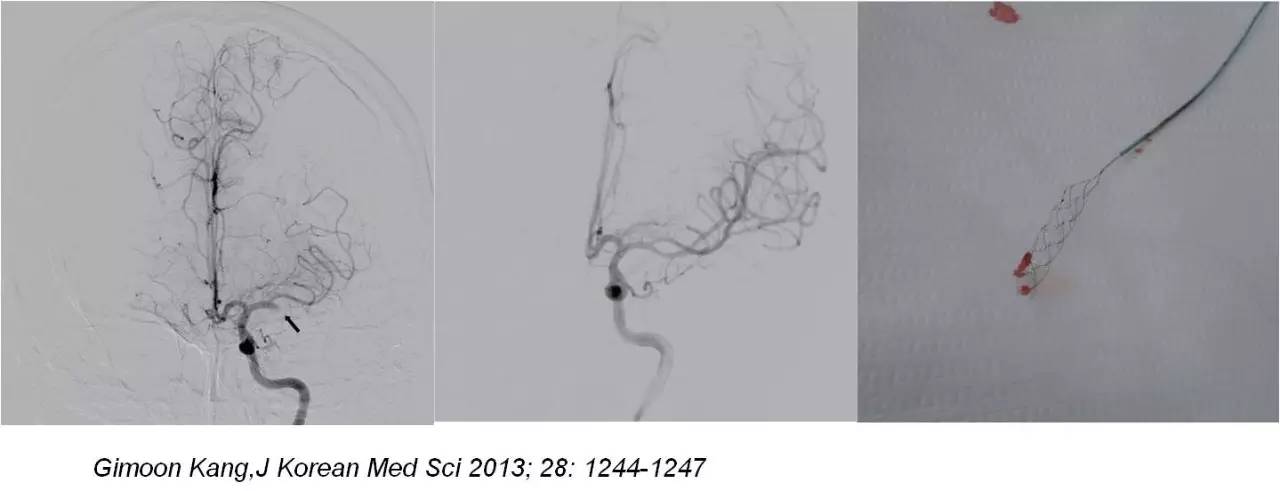

》右侧腹股沟区局部浸润麻醉,常规造影,发现闭塞责任血管后,将微导丝及微导管在导引导管辅助下置于闭塞血管近心端,经微导管注射rt-PA 10-30mg,10min后造影观察血管再通情况 。

》若无再通,微导丝缓慢推进通过闭塞血管,微导管跟进,造影观察闭塞血管远端血管情况,若远端血管通畅,选用取栓支架(Solitaire-AB;ev3 公司,美国)。

取栓治疗何去何从?

mechanical embolectomy in cases of troke due to infective endocarditis manifesting with major neurologic deficits is a subject of controversy and needs additional clinical experience and evaluation in a randomized trials.

取栓治疗对脑梗死所致严重神经功能障碍的疗效需要:

#进一步的临床经验积累

#高质量的随机对照研究